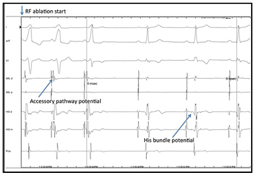

Electro-physiology Study. In the EPS graphic can be seen (arrow) typical signs of a WPW: Intracardiac electrogram showing under right ventricular pacing, atrial activation precocity in distal coronary sinus followed by His bundle (Figure 8-10).

Figure 8 Electro-physiology Study.

Figure 10 ECG 12 Leads and RF Ablation (Images).